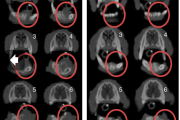

villikesest tekkinud haavand suu limaskestal